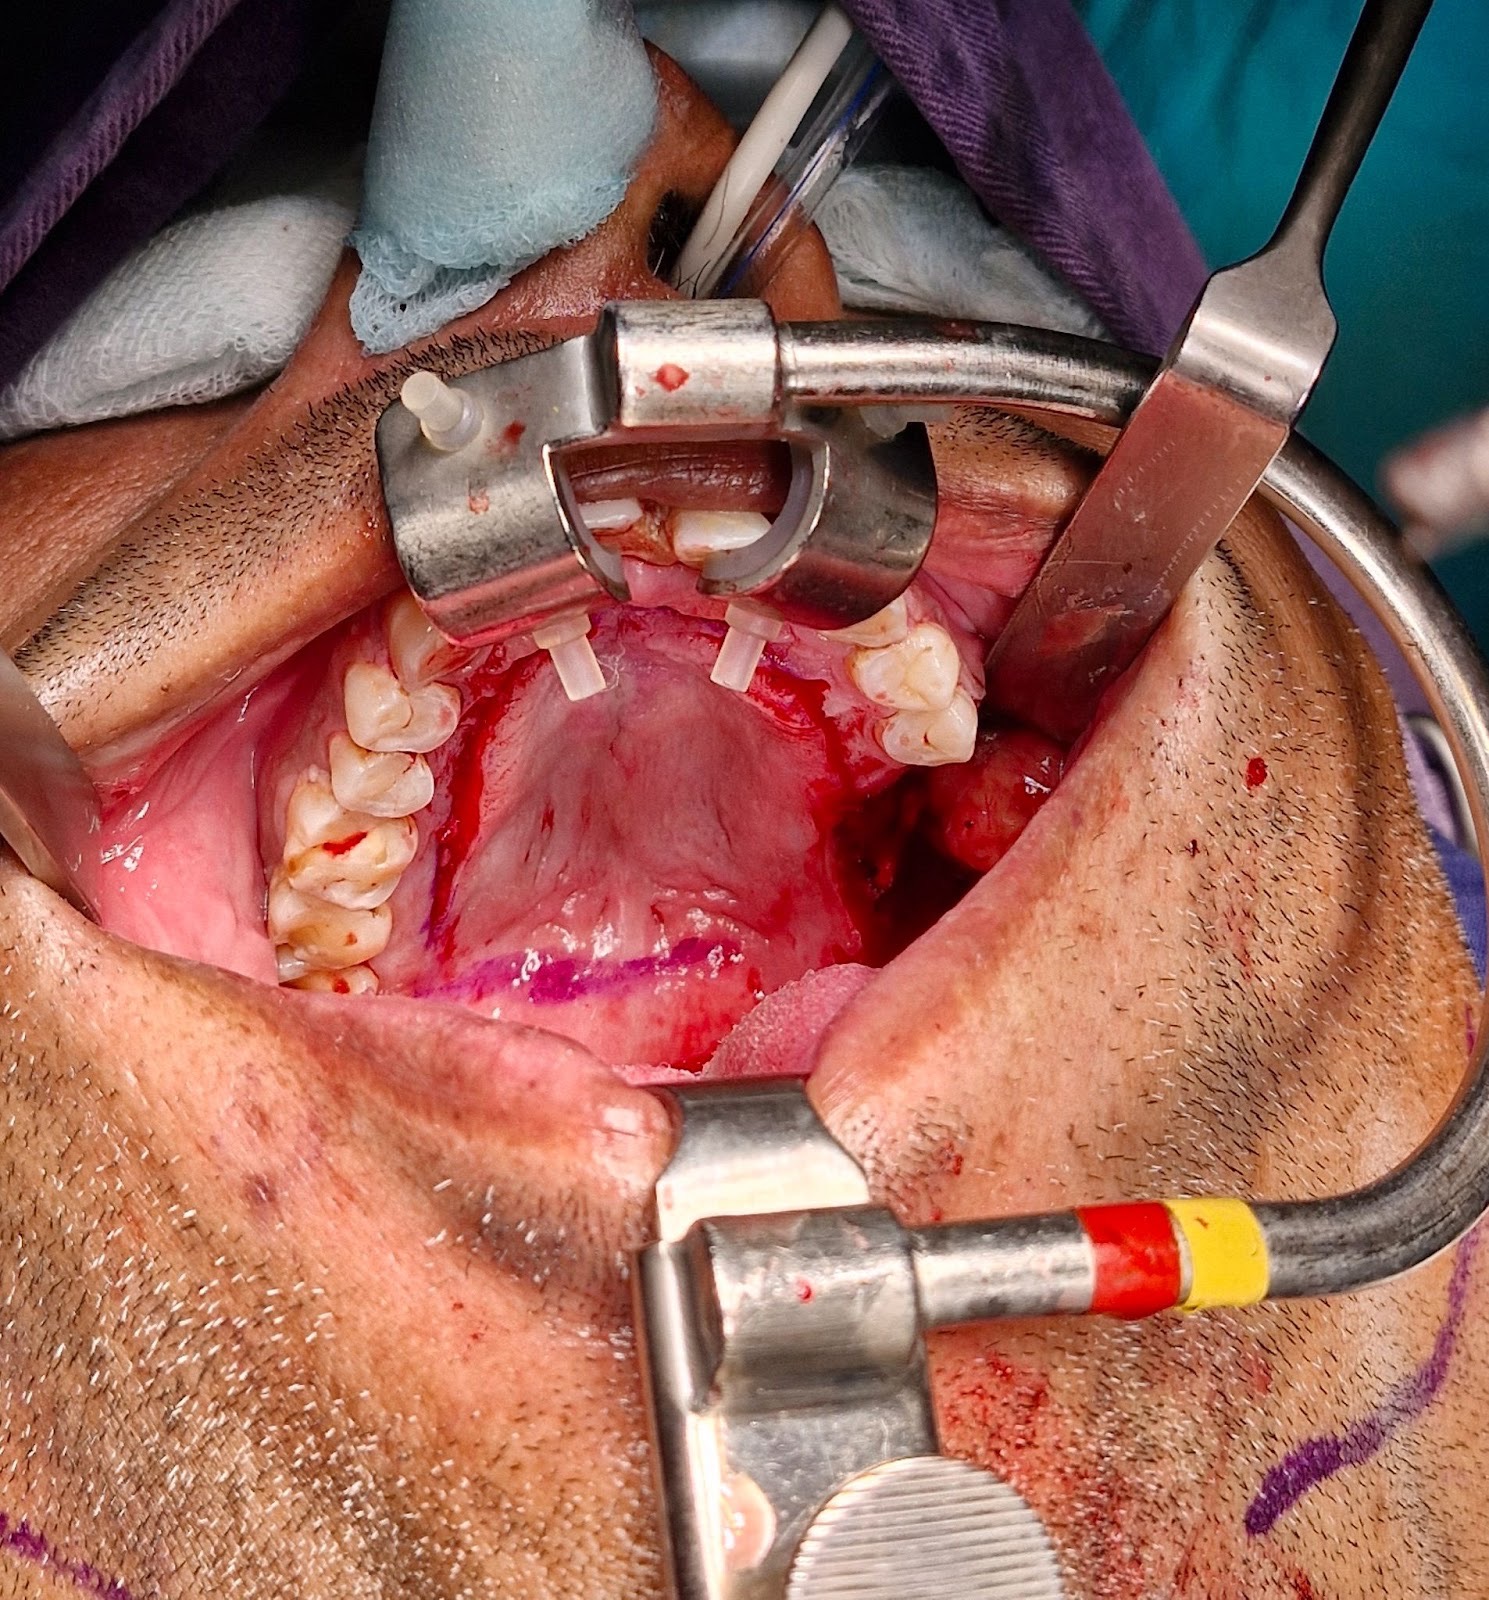

The biopsy proven tumor (SCC) at left retromolar trigione was excised with adequate margins resulting in a defect approximately 3 x 2.5 cm. A sterile marker was used to mark the incisions sparing 5 mm of attached mucoperiosteum. Incision was placed using # 15 blade upto the bone depth and mucoperiosteal flap was raised starting from the contralateral side and towards the vascular pedicle. Posterior releasing incision is made to release the flap for tension free rotation into the defect. Once adequately released, the flap is rotated to cover the defect and secured using Vicryl 4-0 suture. The donor site exposed bone was covered with White Head Varnish (WHV) pack and secured in place using prolene 3-0 suture.